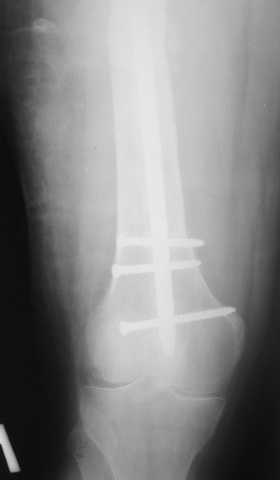

Мы демонтировали спице-стержневой аппарат, рассверлили костно-мозговой канал (до 14 мм), установили в канал спейсер с антибиотиком и произвели его блокирование четырьмя винтами ( рис. 1, 2, 3, 4).

В качестве армирующего элемента для спейсера мы использовали титановый неканюлированный штифт типа UFN (диаметр 9 мм, длина 400 мм). Проксимальную широкую часть штифта костным цементом не покрывали (рис. 5).

Дистальные блокирующие отверстия в цементе рассверлили после его застывания под ЭОП'ом. В проксимальном отломке использовали винт-полер (так как штифт проходил очень близко к переднему кортикальному слою).

В остальном, операция прошла без технических трудностей. Александр Николаевич, спасибо за ваши прекрасные развертки. Так не хочется отдавать их Вам обратно! Завтра пациент выписывается. Температура тела и анализы у него нормальные. Бедро мягкое, отечность тканей значительно уменьшилась. Послеоперационные раны зажили первичным натяжением. Укорочение конечности составляет 1,5 см (по ощущениям больного, это оптимальная длина ноги для него, так как у него анкилоз коленного сустава и голеностопного сустава в положении подошвенного сгибания). Пациент ходит с дозированной нагрузкой на конечность (10% от веса тела). Свищ на передне-наружной поверхности средней трети бедра, который открылся за неделю до последней операции рядом со стержнем аппарата, закрылся 5 дней назад (рис. 6,7, 8).